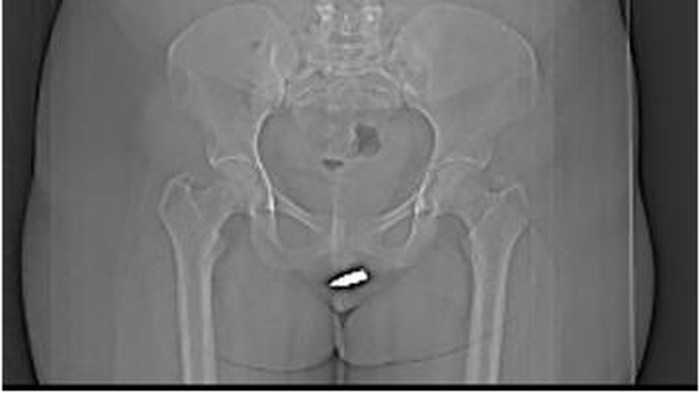

Melihat hal yang dialaminya, wanita 24 tahun itu pergi ke Rumah Sakit Erdoğan di Mogadishu. Di sana, dokter memastikan bahwa peluru yang berukuran dua sentimeter itu bersarang di klitorisnya.

Salah satu cara untuk mengeluarkannya adalah dengan menjalani operasi. Dari hasil CT Scan, peluru itu terlihat jelas dan dapat terasa saat disentuh langsung oleh petugas medis.

Dokter memberinya anestesi lokal dan mengeluarkan peluru di organ intimnya dengan hati-hati. Beruntungnya, operasi yang dilakukan berhasil dan wanita tersebut bisa keluar dari rumah sakit di keesokan harinya dalam kondisi yang baik.